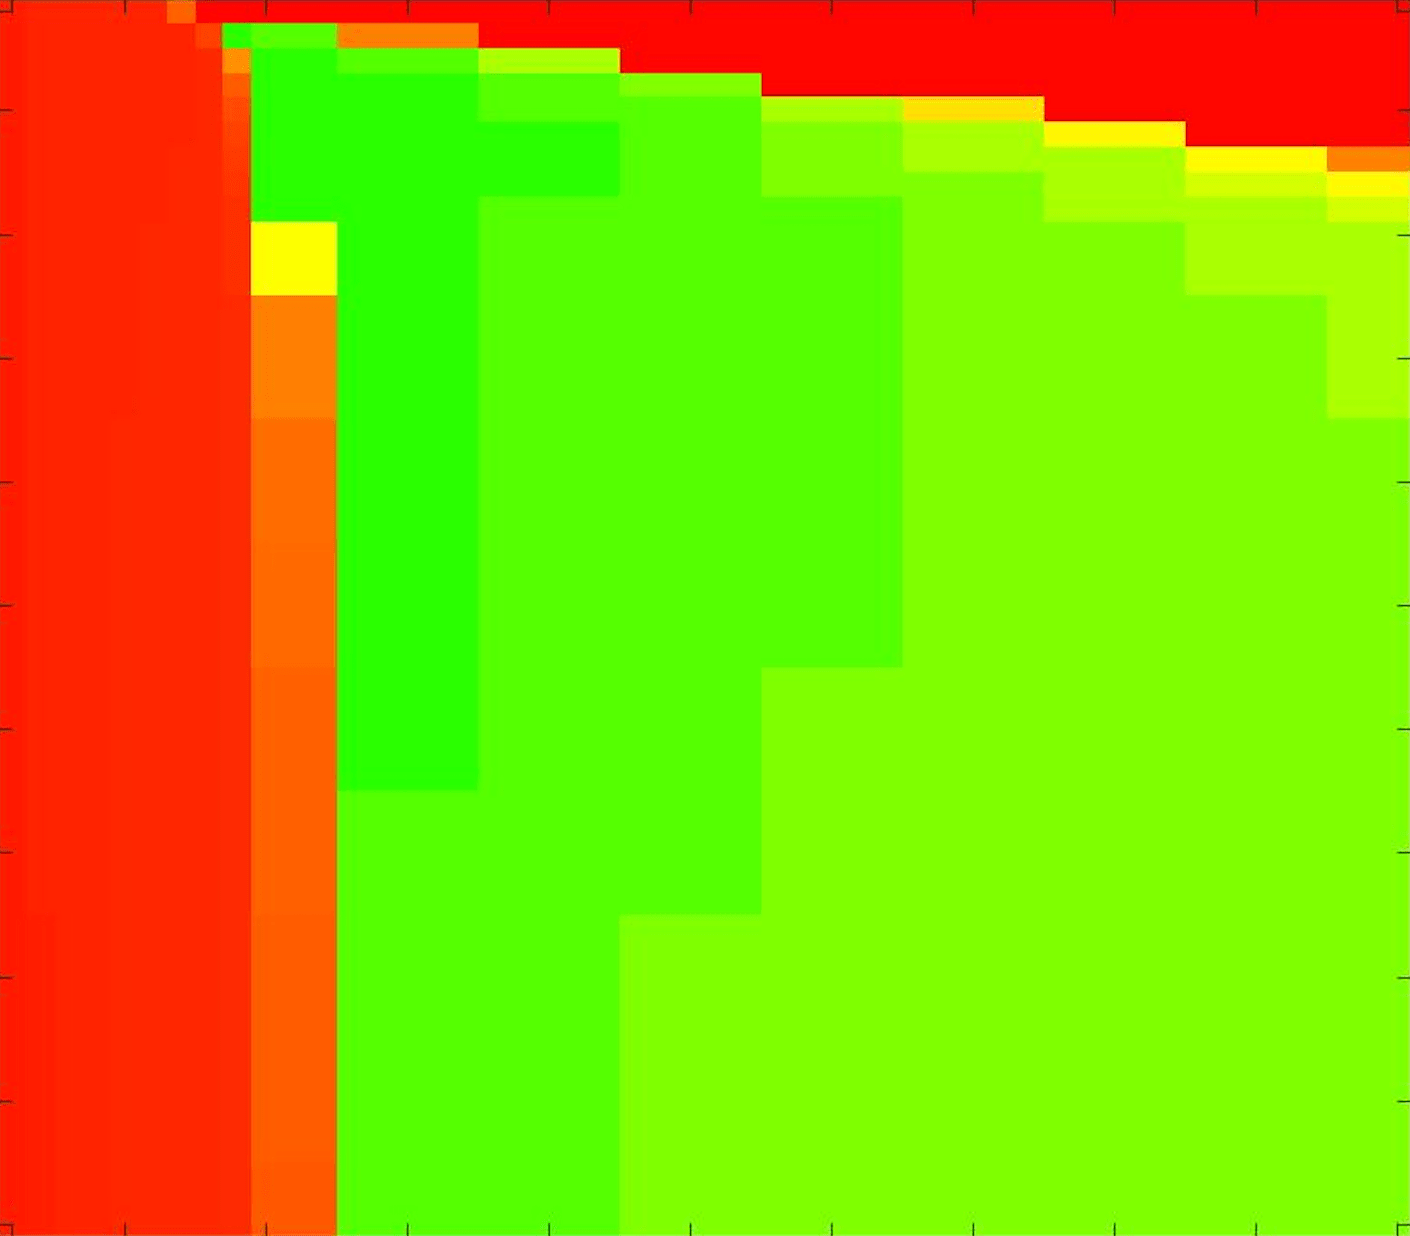

where refers to the number of points in the enclosed region. This takes values in the range , with higher TC values indicating a more accurate segmentation. In the following we will represent accuracy visually from red () to green (), with the intermediate scaling of colours used shown in Fig. 8. This will be particularly relevant in §7.2.

The TC values for the parameter sets are presented as heatmaps in Figs. 11–13. A heatmap is a convenient way to display accuracy results for hundreds of tests concisely. In Fig. 9 we give an example heatmap with the same axes used for those in Figs. 11–13. For each of the combinations of parameter values we give the TC value of the segmentation result and represent it by the appropriate colour. The corresponding colour scale is shown in Fig. 8. Qualitatively, the more green areas of the heatmap the more accurate the model is for a wider set of parameters. Example results for Test Image 5 when varying (with ) for the proposed model are given in Fig. 10. Here it can be seen what each accuracy result corresponds to visually.

Note. The axes have been removed from the heatmaps in Figs. 11–13 for presentational clarity. However, to be explicit, the axes used in all heatmaps are the same as those in Fig. 9.

Synthetic Images. These results are presented in Fig. 11. For Test Images 1–2 we see poor parameter robustness from all competing models, except for GAV which performs reasonably well. However, the proposed model has minimal parameter sensitivity for these images, with good results achieved for almost every combination of values tested. For Test Image 3 all models have a reasonable parameter range (except for RSF), however the proposed model gives better quality results for a wider parameter range. The other models achieve reasonable results here as the foreground intensity of the ground truth is greater than the background , whereas for Test Images 1–2 they are equal . These results highlight the key advantage of the proposed model.

Real Images. In Fig 12 we present results for Test Images 4–6. Here, the proposed model performs in a similar way to its competitors because these images are more typical selective segmentation problems in the sense that there is a clear distinction between the foreground and background intensities. In particular, the values in each case are: Test Image 4 , Test Image 5 , and Test Image 6 . It can be seen that the proposed model is competitive compared to previous approaches. The performance is quite poor for Test Image 5, but is arguably still the best for this challenging case. In Fig. 13 we present results for Test Images 7–9. Here the proposed model outperforms previous approaches significantly for each image. This is mainly due to the type of image considered. Specifically, the true intensities are: Test Image 7 , Test Image 8 , and Test Image 9 . The proposed model is capable of achieving results where , with other models failing completely in these cases.